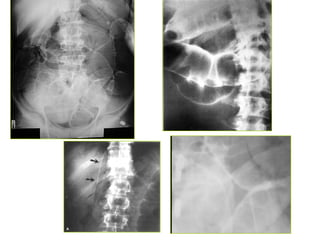

*Daáu hieäu: daõn, tröôùng hôi vaø dòch

1. Ruoät non > 3cm

2. Ruoät giaø > 6cm, manh traøng > 8cm

3. Möïc nöôùc – hôi ( xuaát hieän töø 12-24giôø)

4. Thaønh ruoät phuø neà ( >3mm)

5. OÅ buïng môø (dòch trong oå buïng)

Phaân bieät möùc nöôùc hôi trong:

1. Taéc ruoät non:

- Naèm ôû trung taâm: hoá chaäu (P)  haï söôøn (T)

- Chieàu roäng > chieàu cao

- Caùc neáp maûnh, naèm gaàn nhau

- Nhieàu quai ruoät, kích thöôùc nhoû

2. Taéc ruoät giaø:

- Naèm ôû ngoaïi vi

- Chieàu cao > chieàu roäng

- Caùc neáp daøy, ít

- Vaøi quai ruoät voùi kích thöôùc lôùn

- Veà sau keøm theâm taéc ruoät non